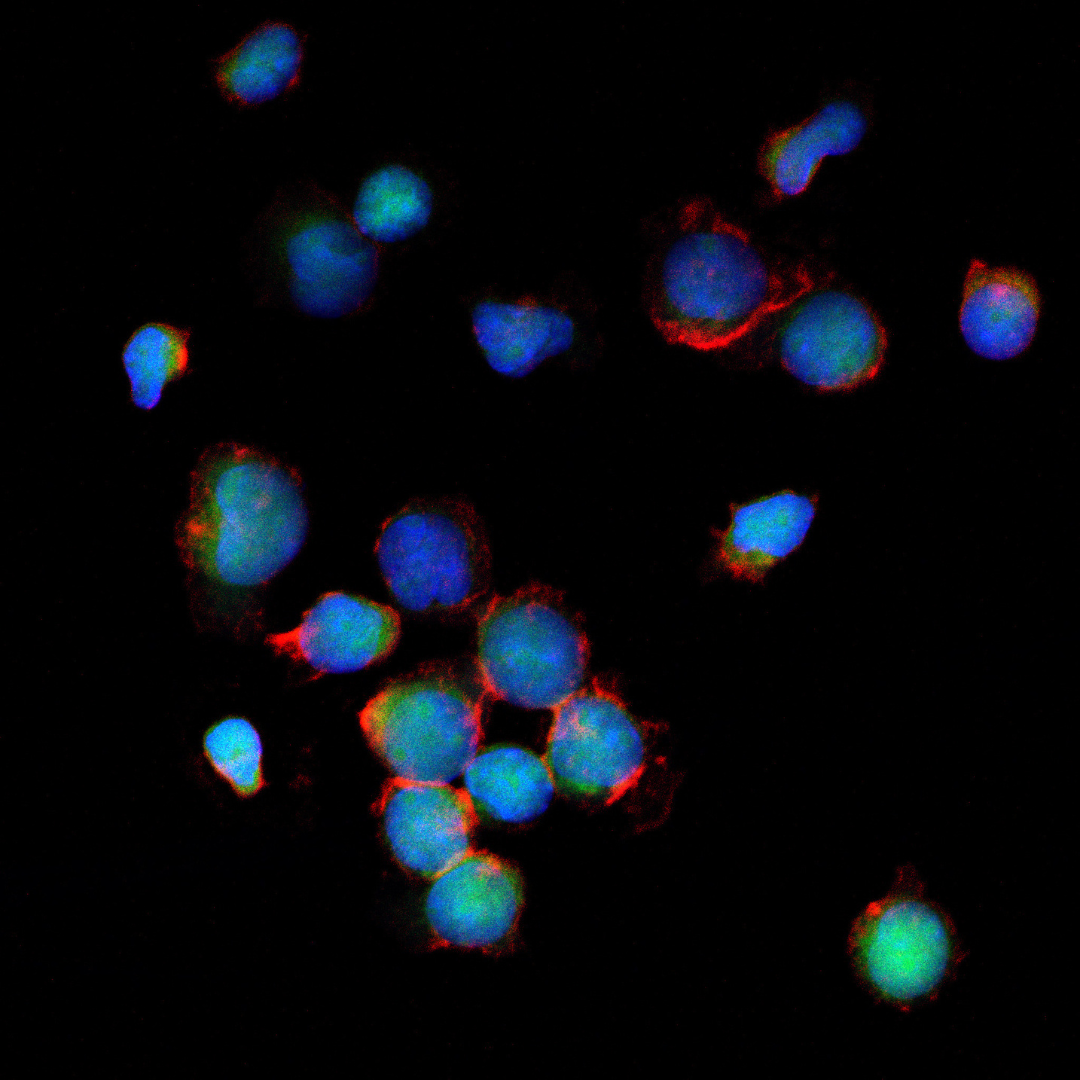

Buy My Cancer

Za nietypowe myślenie i nieszablonowe podejście wykorzystujące sztukę i ilustrację w nowoczesnym świecie technologii. Szczególnie warto to docenić, bo dla obu bardzo ważne są nowe drogi dotarcia do odbiorcy i fajnie, że twórcy kampanii o tym myślą. Wyróżnienie należy się za nowoczesne podejście, za “spojrzenie inaczej”, za przecieranie nowych dróg wykorzystania ilustracji i znalezienie nowego miejsca we współczesnym, zdigitalizowanym świecie. I na koniec, oczywiście, za szczytny cel, bo jeśli ilustracja może pomóc, to cieszy mnie to jeszcze bardziej.